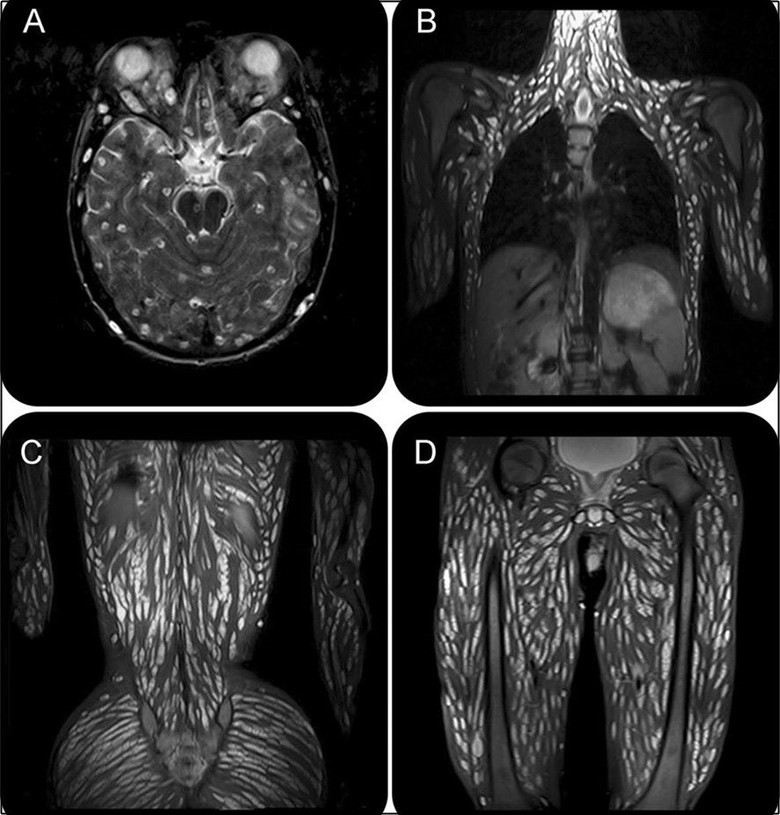

Sau những chẩn đoán ban đầu, bác sĩ cho tiến hành chụp cộng hưởng từ MRI và phát hiện ra mô não, đầu, ngực, bụng và chân tay của bệnh nhân phủ đầy sán dây, trông cực kỳ khủng khiếp. Bệnh nhân được xác nhận là nhiễm cysticercosis (bệnh nhiễm ấu trùng sán dây lợn).